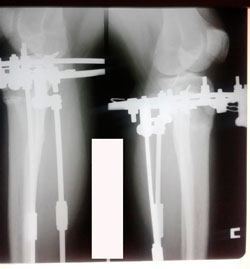

Исходник - 36 лет

Дата операции - 13.03.2020

Вложения

image-12-03-20-07-00.jpg

image-12-03-20-07-00-6.jpg